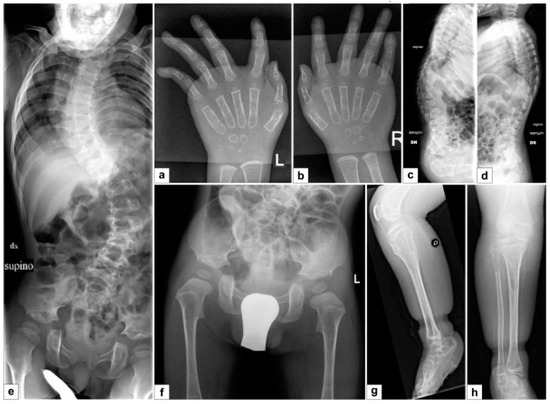

- the extreme distal joint hypermobility and soft, hyperextensible skin, particularly of the hands;

- the radiological signs, which are the main indicator for discriminating spEDS-B4GALT7, associated with radioulnar synostosis, and spEDS-B3GALT6, characterized by kyphoscoliosis (congenital or early onset and progressive) and by the skeletal signs of SEMDJL1 (platyspondyly, short iliac bones, elbow dislocation).